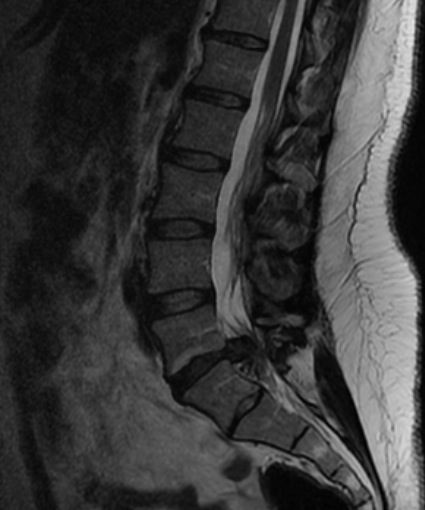

Hernie Discale Lombaire

Elle a pour but de libérer la racine nerveuse de la compression et se déroule le plus souvent sous anesthésie générale. Le chirurgien accède au disque par une courte incision (3 à 4 cm), en écartant latéralement la ou les racines ; il retire la hernie discale, vide le centre du disque, pour éviter qu’un fragment libre ne se mobilise et entraîne une récidive de la compression. Le disque n’est jamais entièrement enlevé.